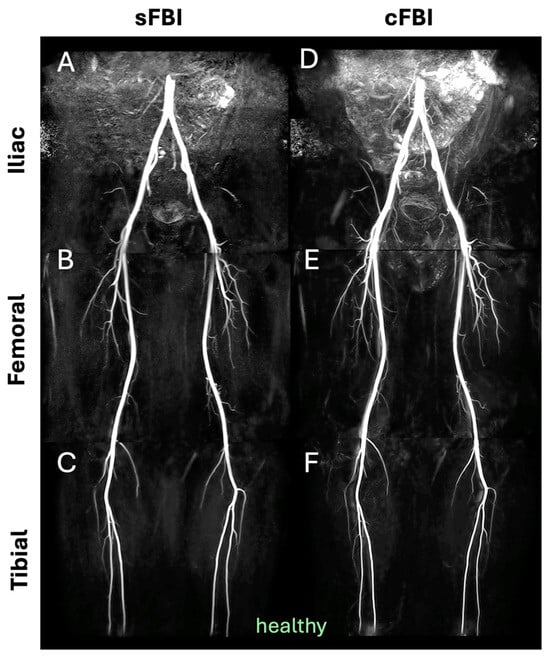

Three-Station Non-Contrast MR Angiography of the Lower Extremities Using Standard and Centric Fresh Blood Imaging

3. Results